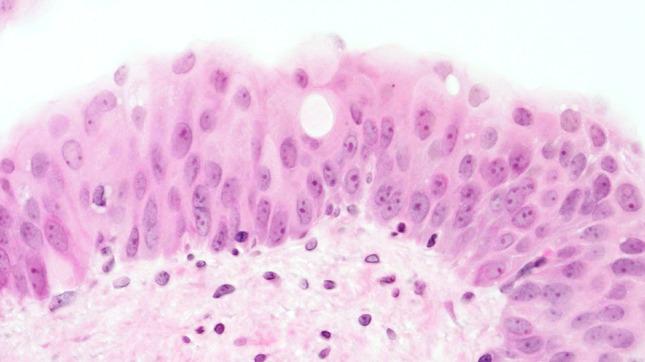

The morphology of experimentally induced urinary bladder precancerous lesions has been differentially interpreted in the literature. Here, we aimed to describe the development of precancerous lesions of the urothelium histologically and by DNA cytophotometric analysis.

We induced precancerous lesions of the urothelium in 60 Wistar rats with 0.05 % N-butyl-N-(4-hydroxybutyl)nitrosamine (BBN) solution as drinking water. After exposure for 2-20 weeks, each animal received tap water for 2 weeks. Subsequently, six animals were killed every 2 weeks, and urothelia of three urinary bladders per time point were examined by DNA cytophotometry of smear preparations. An additional three urinary bladders were processed for histological analysis.

Over 20 weeks, BBN exposure led to a significant difference between the control group and most of the BBN-exposed 2-week groups and to differences between most of these time point groups. After week 4, this difference included a higher proportion of cells with increased nuclear DNA content. At the end of the experiment, DNA cytophotometric values of the urothelium in experimental rats corresponded to those of poorly differentiated urothelial carcinomas.

Biologically significant stages of precancerous lesions were already detectable after 4 weeks of BBN exposure, considerably earlier than previously described in the literature.